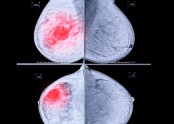

- ■ 정기적으로 유방촬영하는 것이 왜 중요할까요?    ① 아래 환자분은 30대 중반에 검진상 양성 석회화가 있던 분으로 5년 되던 40세에 국가암 검진을 했고, 이때 과거에는 보이지 않던 소견으로 유방촬영 하부 작은 부위에 …

|